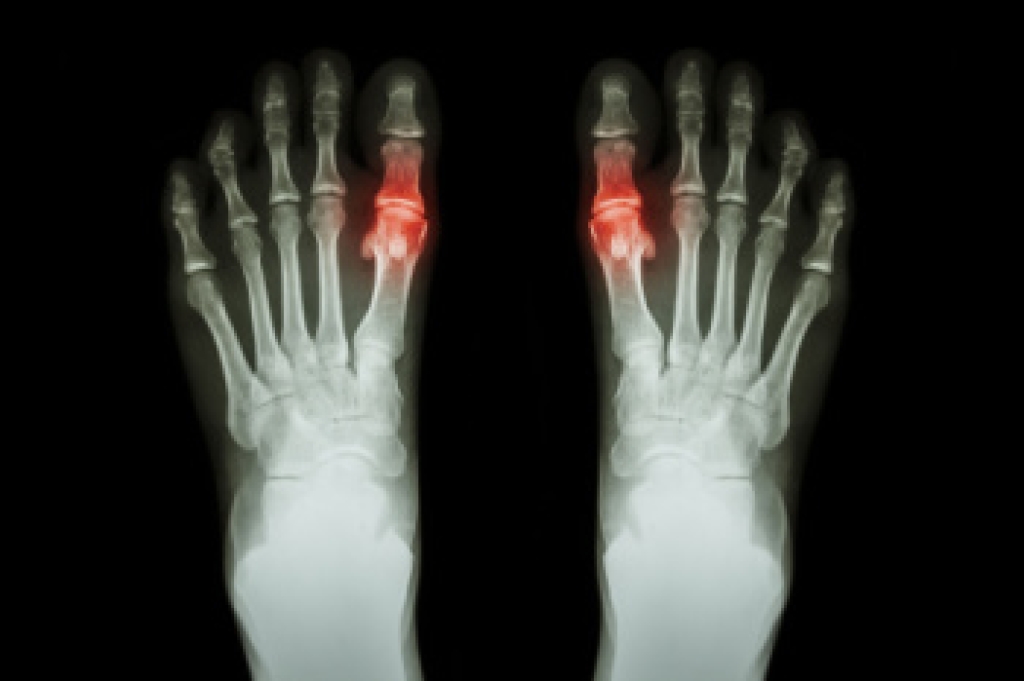

Gout and How It Differs From a Bunion

Gout is a form of inflammatory arthritis caused by the buildup of uric acid crystals in the joints, most often affecting the big toe. It differs from a bunion, which is a structural deformity where the big toe gradually shifts inward due to joint misalignment. Gout commonly affects men, postmenopausal women, and individuals who consume high purine foods such as red meat and certain seafood. Symptoms include sudden, intense pain, redness, swelling, and warmth in the affected joint. Risk factors include obesity, kidney disease, alcohol intake, and genetics. A podiatrist can diagnose the condition, manage flare ups, recommend dietary changes, and provide medications or supportive footwear to reduce pressure on the joint. If you have symptoms of gout, it is suggested that you are under the care of a podiatrist who can help you to manage this painful condition.

What Is Gout?

Gout is a form of arthritis that is characterized by sudden, severe attacks of pain, redness, and tenderness in the joints. The condition usually affects the joint at the base of the big toe. A gout attack can occur at any random time, such as the middle of the night while you are asleep.

Symptoms

- Intense Joint Pain - Usually around the large joint of your big toe, and it most severe within the first four to twelve hours

- Lingering Discomfort - Joint discomfort may last from a few days to a few weeks

- Inflammation and Redness -Affected joints may become swollen, tender, warm and red

- Limited Range of Motion - May experience a decrease in joint mobility